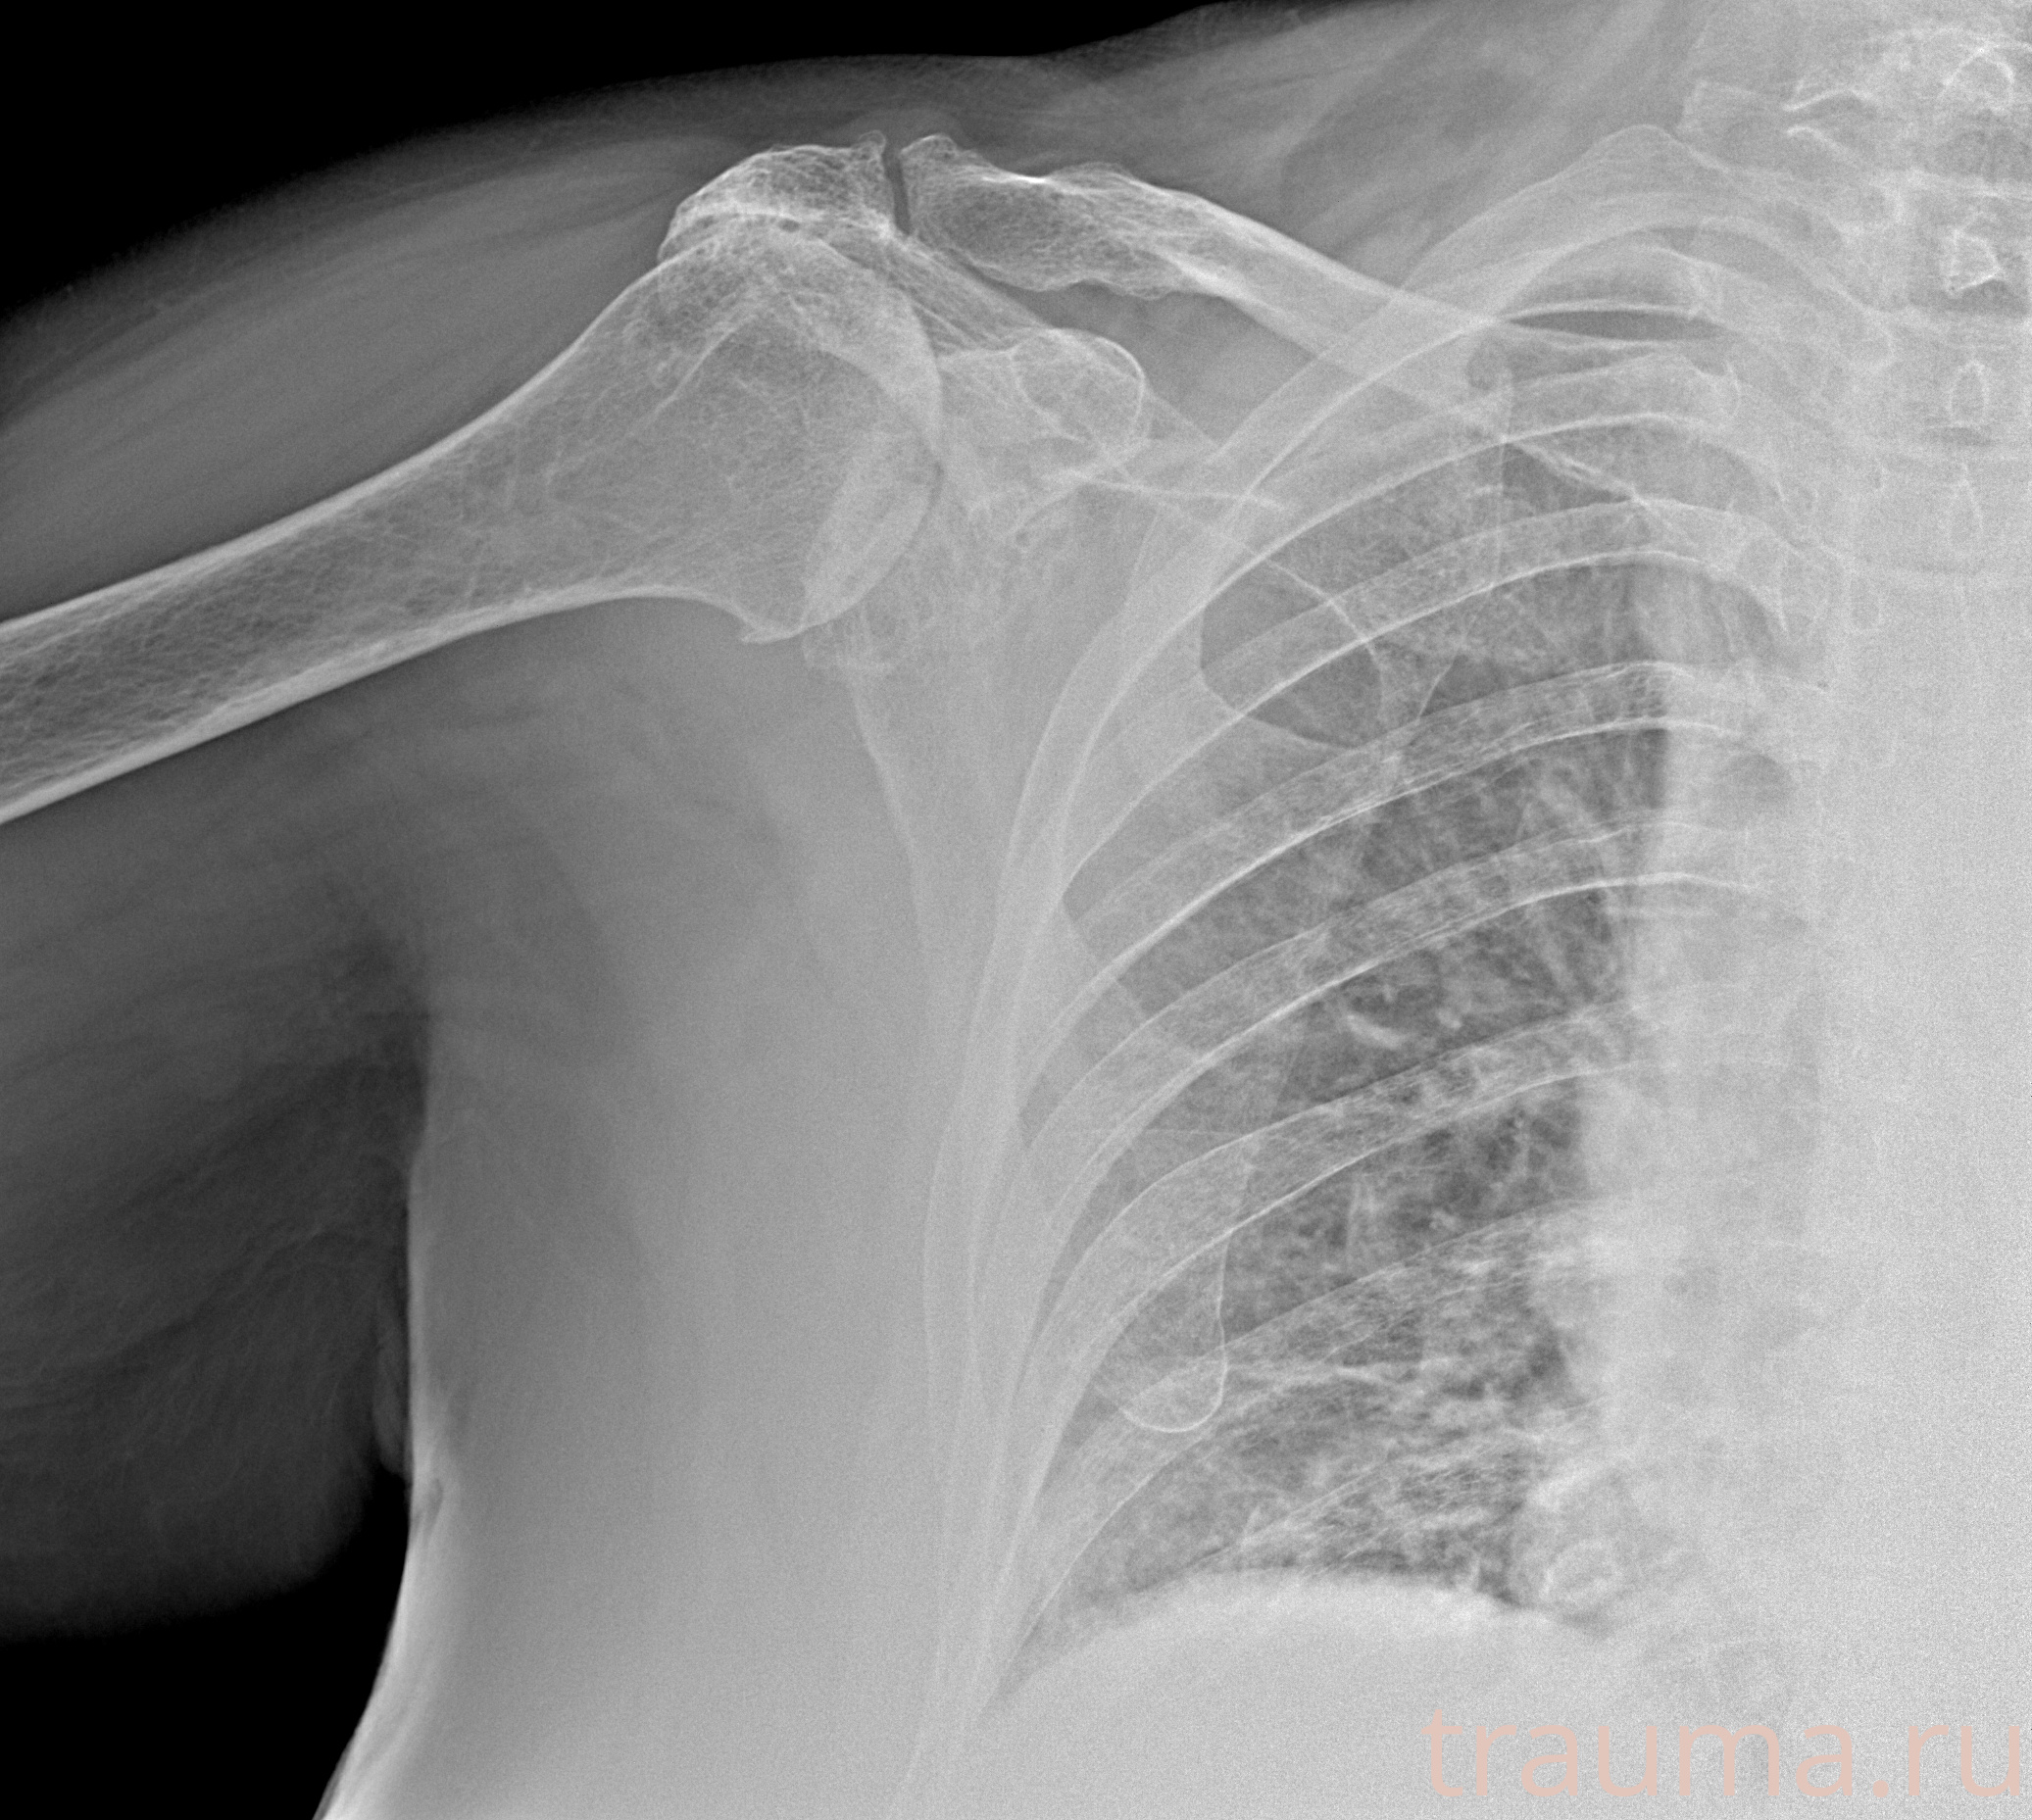

Рентгенограммы

Рентген на дому: по вашему адресу приезжает врач-рентгенолог, травматолог-ортопед с мобильным рентгеновским аппаратом, проводит диагностику травмы или заболевания, делает необходимые рентгенограммы, дает рекомендации по дальнейшему лечению. Получить качественные снимки в домашних условиях возможно благодаря уникальной методике, разработанной МосРентген Центром для института  Склифосовского